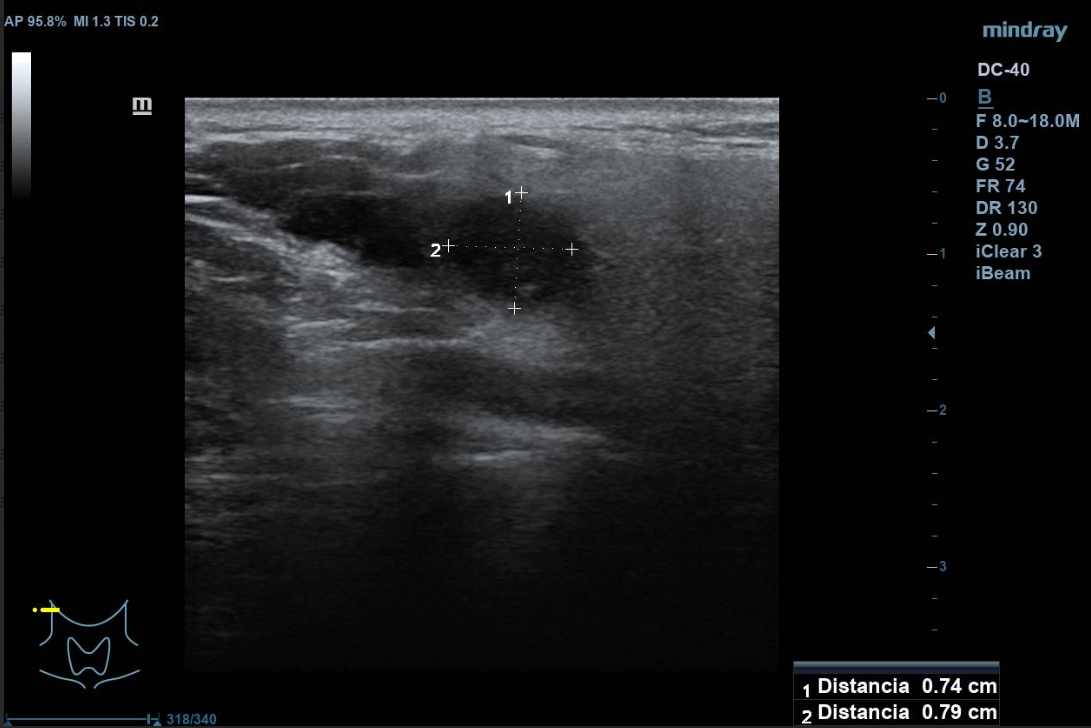

Se aprecian al menos dos lesiones intraparotídeas, una menor hipoecogénica, redondeada de unos 10 mm de diámetro máximo, doppler con vascularización mixta. La mayor de unos 3 cm de diámetro máximo, hipoecogénica, de contenido irregular, con áreas anecogénicas, de características sólidas, bien definido. Vascularización mixta, central y periférica. No se observan adenopatías cervicales de aspecto ecográfico patológico. La parótida contralateral, impresiona de normalidad.